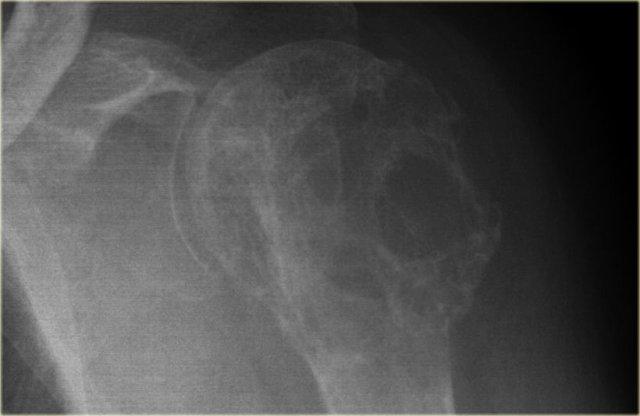

SBC: well-defined osteolytic lesion without expansion of the proximal meta-diaphysis of the humerus with pathologic fracture

Solitary Bone Cyst

Nang xương đơn độc, còn được gọi là nang xương đơn buồng, là một nang xương thực sự.

Nhiều tổn thương tiêu xương giới hạn rõ thường được gọi là dạng nang, nhưng đây là cách gọi không chính xác.

Nang xương đơn độc thường biểu hiện bằng gãy xương.

Đôi khi có thể thấy hình ảnh mảnh xương gãy rơi xuống (fallen fragment).

Vị trí hay gặp: đầu trên xương cánh tay và xương đùi.

Thường ít giãn nở hơn so với nang xương phình mạch.

Chẩn đoán phân biệt: nang xương phình mạch, loạn sản xơ dạng nang.

Nang xương đơn độc có thể di chuyển từ vùng hành xương đến thân xương trong quá trình phát triển của xương.